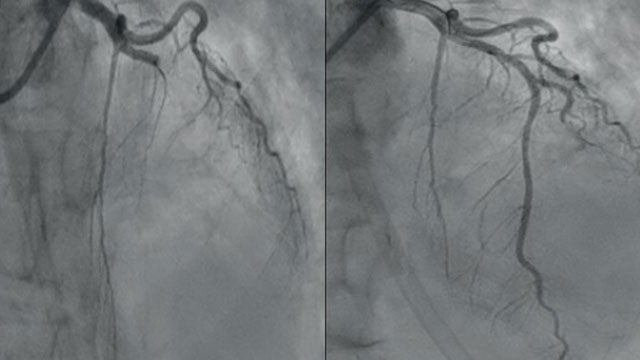

How to perform angiographic check after large-sheath removal in single access procedures

In the absence of other arterial access, this step-by-step tutorial shows how to perform anterograde angiography of the arterial axis after removal of the large sheath, making it easier to recognise and rapidly manage vascular complications such as arterial lesions and haemostasis failure.